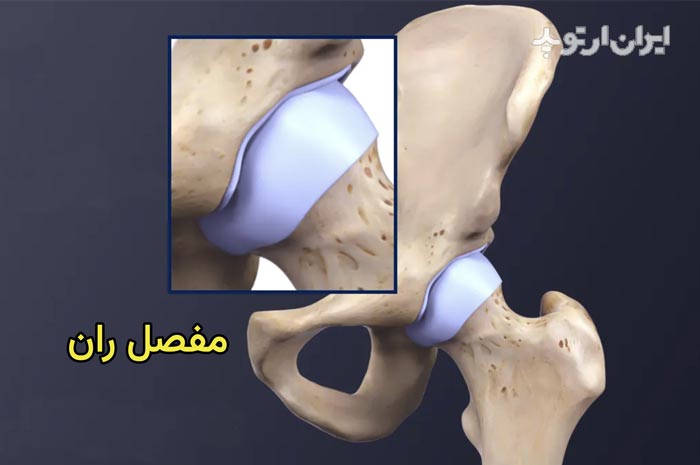

مفصل ران یا مفصل لگن یکی از مهمترین مفاصل بدن بوده و محل اتصال تنه و لگن به استخوان ران است.

مفصل ران وزن بدن را تحمل میکند. و نقش اصلی در هنگام راه رفتن با این مفصل است. خرابی مفصل ران موجب درد و لنگش و بد راه رفتن میشود.

مفصل ران از کنار هم قرار گرفتن دو استخوان بوجود میاید. در قسمت بالا حفره استابولوم قرار دارد که قسمتی از لگن خاصره است. این حفره بشکل تقریبی یک نیمکره است. در داخل حفره استابولوم سر استخوان ران قرار گرفته است.

سر استخوان ران بالاترین قسمت استخوان ران است که به شکل گرد و کروی است. وقتی مفصل ران به علت آرتروز و یا روماتیسم خراب میشود معمولا هم قسمت کاسه ای یعنی حفره استابولوم و هم قسمت کروی یعنی سر استخوان ران هر دو خراب میشوند.